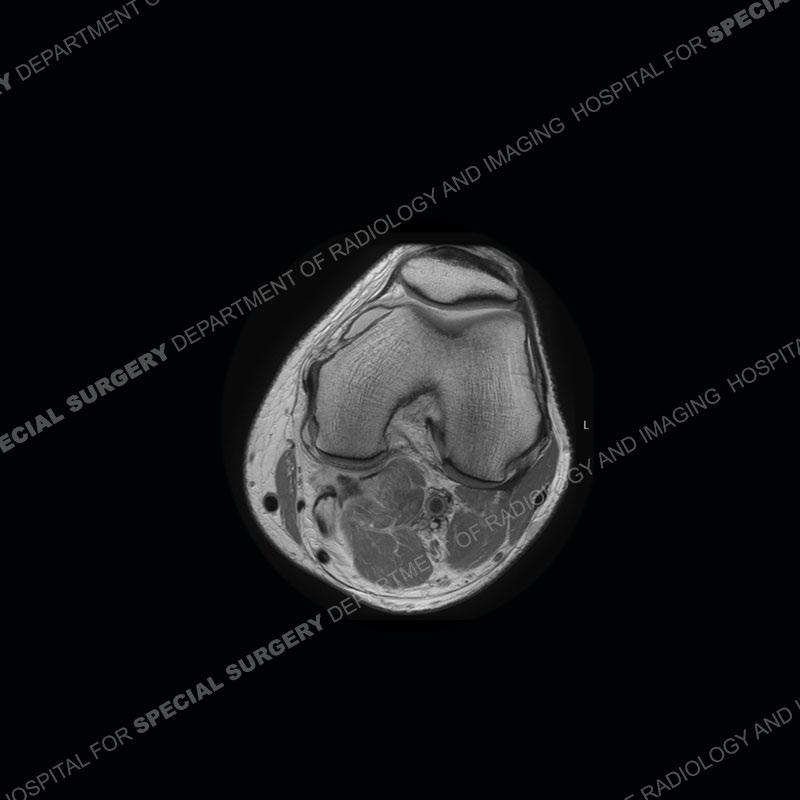

Findings

The radiographs show degenerative change of the medial compartment and a varus knee, but they are not germane to this case. No acute bony injury is present. The MRI shows edema of the posterior medial knee/soft tissue and a focal area of a partially disrupted low signal structure. The details are kept at a minimum in the findings of this case on purpose.

Diagnosis: Partial Disruption Medial Head Gastrocnemius (MHG)

The findings were kept purposefully vague as identifying the structures early on takes away a lot of the diagnosis. An uncommon entity and one of which we do not see a lot. Enthesopathic changes and tendinosis are seen as are distal MHG injuries, but proximal tears are rarely present. This case highlights a number of points. One, it almost always comes down to anatomy. Perhaps not a structure we normally spend too much time on, except save for diagnosing a Baker’s cyst, but knowing where this structure and all structures exist in all three planes is imperative. Second, when you think you are making a “call” or finding that you have never made before, step back and think is this just the abnormal presentation of a common pathology. That situation arises much more frequently. Third, if you look at it once, twice, and probably a third time and are confident in your odd or very rare diagnosis, stick to your guns. Especially, when it comes down to anatomic structures, the proof will be in the images.

Fourth, use all imaging planes and different pulse sequences to make your diagnosis. The edema highlighted in this case can be seen as the obscuration of fat on the PD images but is much easier to perceive as the high signal on the IR pulse sequences. The actual disruption of the MHG myotendinous junction is only able to be seen on the axial images. On the sagittal and coronal images, we get a sense something is wrong but hard to be exact. Lastly, when you look at a study and something just seems off (as I would say the sagittal and coronal images do with that dark band of tissue posteriorly), listen to yourself and go through the study slowly and meticulously. Most of the time you will find you were right, and something indeed is present.